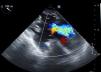

Her TEE showed biatrial dilatation, mild aortic regurgitation, a normally implanted and adequately functioning mitral valve prosthesis, moderate-to-severe TR and preserved biventricular function (Figure 1).

Prior to implantation, her TEE showed a tricuspid annular area of 13 cm2 and an effective regurgitant orifice (ERO) area (calculated by the proximal isovelocity surface area [PISA] method) of 0.4 cm2.

A follow-up TEE showed mild-to-moderate TR, with an ERO area (calculated by PISA) of 0.2 cm2 and a regurgitant volume of 18 mL (Figure 3), and preserved RV function.